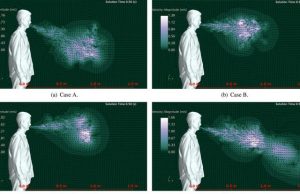

Researchers identify features that could make someone a virus super-spreader

New research from the University of Central Florida has identified physiological features that could make people super-spreaders of viruses such as COVID-19.

In a study...